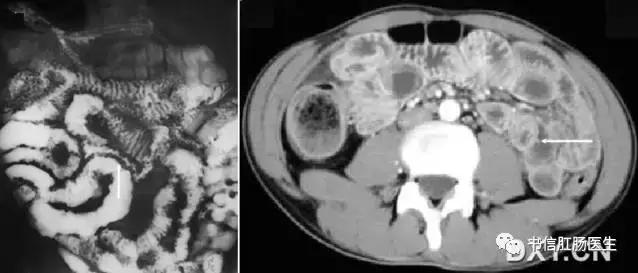

★ 左图:克罗恩病 X 线小肠钡剂灌肠,病变肠腔不规则狭窄(白色箭头),段壁僵硬,呈节段性分布;右图:CT 横断面示小肠肠壁节段性增厚,肠腔狭窄(白色箭头)。

■ 影像表现:在小肠钡剂检查中,小肠形成类似于粗糙棉线一样的细钡线。

■ 征象解析:胃肠道严重狭窄,导致内腔呈线样改变,胃肠细绳征经常作为内腔狭窄的一个术语,最初用于描述克罗恩病的可逆性狭窄。狭窄原因是由于严重溃疡引起易激和痉挛所致的不完全性梗阻,且可以发现狭窄与扩张交替。当狭窄主要由水肿和痉挛引起时,狭窄程度不是一致的,如小肠壁因纤维化而增厚,则肠腔的内径表现为一致变窄。黏膜被纤维坏死组织所替代,偶尔黏膜岛仍可被发现。

■ 讨论:胃肠细绳征己被证实为克罗恩病的特征性表现,最常出现在末段回肠。早期克罗恩病的肠道异常包括粗绒毛征、皱襞增厚和阿弗他溃疡。沿着肠系膜缘的线样溃疡是小肠克罗恩病最重要的影像特征之一,溃疡平行于短缩的、凹入的或者僵直的肠系膜缘。相邻的肠系膜增厚和回缩,特别在有受侵肠段的连接处。胃肠细绳征的出现高度提示克罗恩病,但它也可在其他疾病中出现。